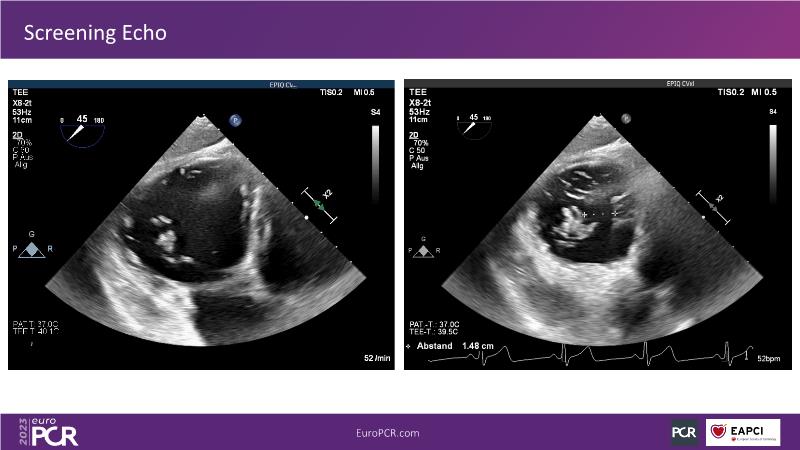

Heterotopic valve replacement for patients with right heart failure and tricuspid regurgitation - All you need to know!

Discover the comprehensive guide to heterotopic valve replacement for patients experiencing right heart failure and tricuspid regurgitation. Join this session to gain insights into patient selection criteria, delve into the concept behind this innovative procedure, and grasp the fundamental aspects of its execution.

- To perform patient selection